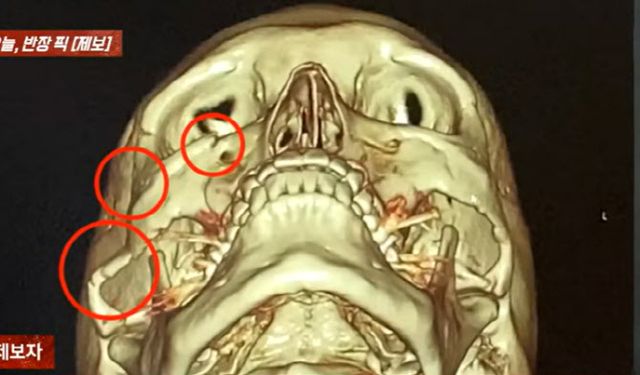

이 사고로 크게 다친 A씨는 광대뼈 함몰, 안와골절 등 전치 6주의 상처를 입어 현재 수술까지 진행한 상태다.